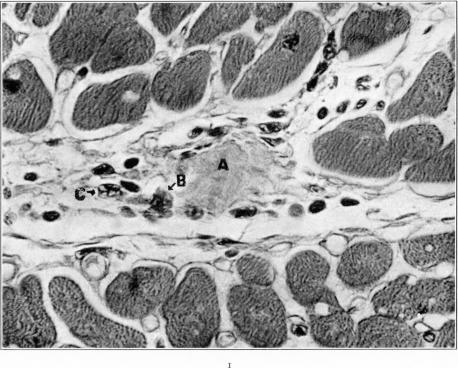

Studies on the Myocardial Aschoff Body: I. Descriptive Classification of Lesions.

Am J Pathol. 1934 Jul;10(4):467-488.15.

Studies on the Myocardial Aschoff Body: I. Descriptive Classification of Lesions.心肌阿绍夫小体的研究:I. 病变的描述性分类